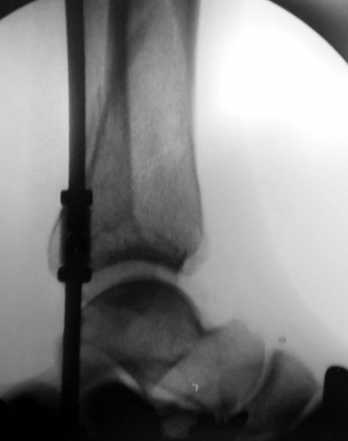

Пример - довольно похожий перелом, оперированный в первые 8 часов после аварии у 40-летнего больного, страдающего тяжёлым сахарным диабетом 1 типа.